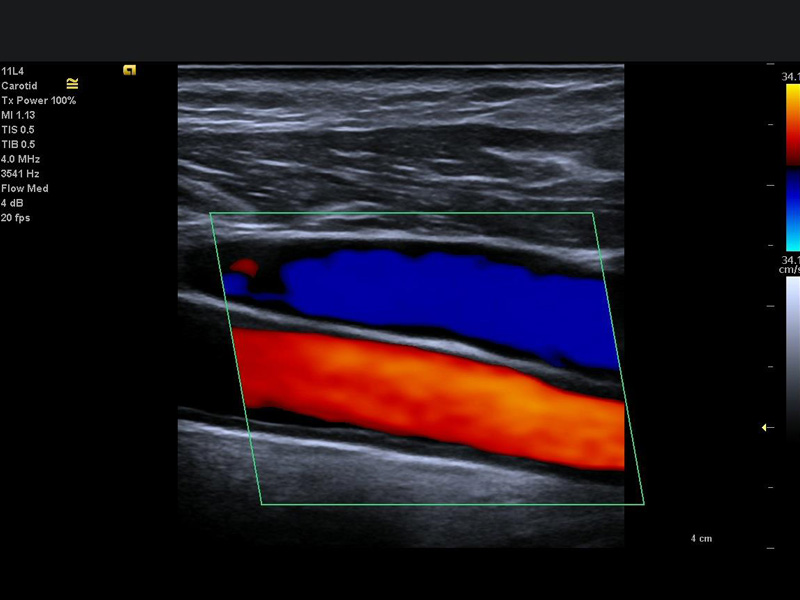

Doença ateromatosa carotídea aumenta risco de AVC

Doença ateromatosa carotídea, ou ateromatose carotídea, é a deposição nas artérias carótidas, que cursam no pescoço e levam o sangue tanto para a cabeça quanto para o cérebro, de cristais de colesterol. Um grau muito avançado dessa deposição pode levar à estenoses (redução do calibre) da artéria, e consequentemente menor passagem de sangue, que pode contribuir para o acidente vascular cerebral (AVC). Mesmo placas não muito grandes, quando não estão calcificadas, podem estar mais suscetíveis à “soltar” uma parte, que pode migrar para uma pequena artéria cerebral, e determinar uma paralisia, por exemplo, as chamas placas “moles”, ou ulceradas. Para avaliar a presença e o grau de obstrução dessas e de outras artérias em nosso corpo o exame de ultrassom Doppler é muito solicitado pelos médicos, principalmente cardiologistas e neurologistas, para que possam, quando necessário, ajustar medicações ou mesmo indicar procedimentos endovasculares (por “cateterismo”) ou cirúrgicos para o paciente. O ultrassom Doppler é um exame indolor, que não exige internação hospitalar nem mesmo a injeção de medicamentos, sendo que os modernos equipamentos disponíveis no mercado, quando operados por médicos capacitados, apresentam excelente acurácia diagnóstica.